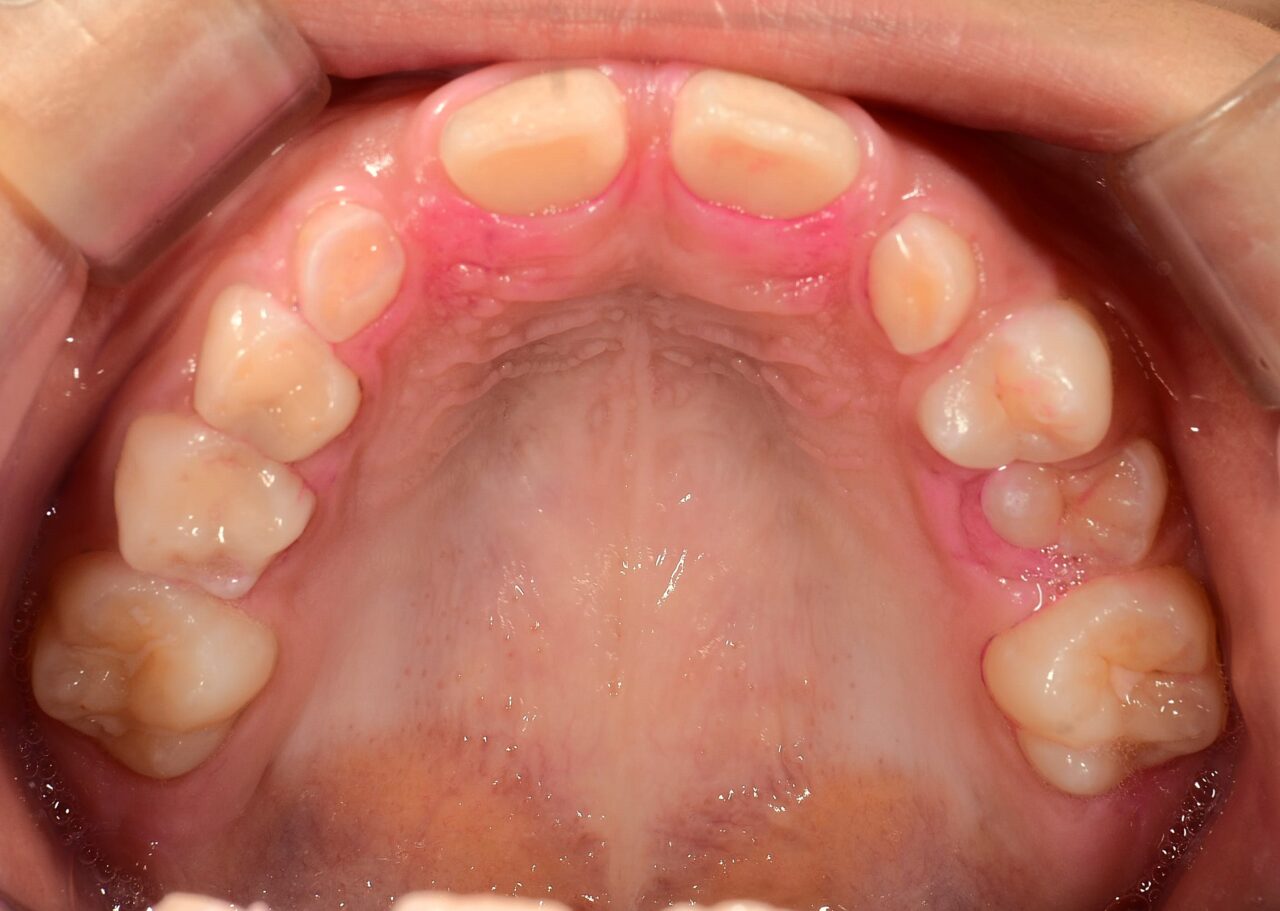

上顎が小さく永久歯が生えるスペースが無い

• before

• after

年齢 7歳(小学2年生)

性別 男の子

主訴 上顎の前歯に隙間が有ることを心配したご両親がご相談にいらっしゃいました。

治療 現在治療中

隙間が有る事よりも、顎が小さく永久歯が骨の中に埋もれ、萌出障害が起こっている事が問題でしたので、保隙・側方拡大を行い、永久歯がスムーズに萌出できるよう1期治療を行いました。

備考 1期治療¥400,000

別途調整料¥5,000/1~1.5月

二期治療(ワイヤー装着)¥400,000

別途調整料¥6,000/1~1.5月

※患者様から承諾を得て掲載しております。